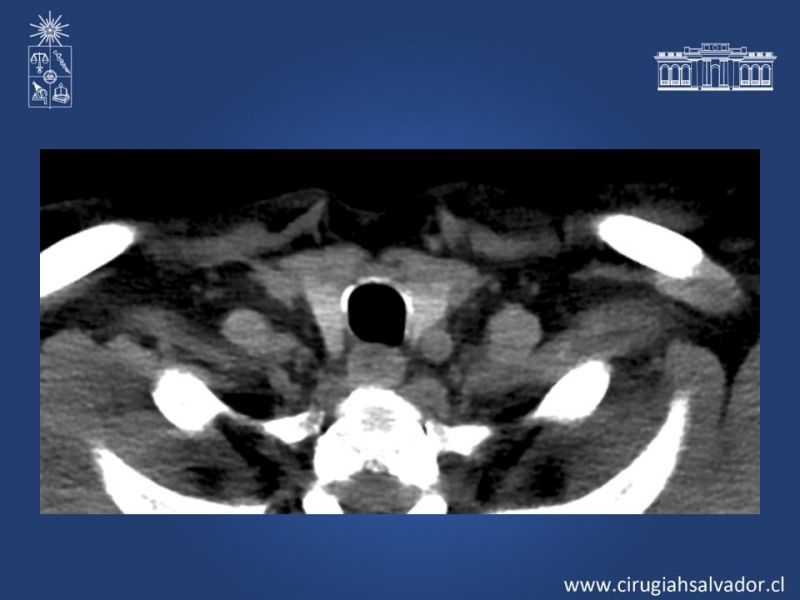

Stents de Vía Aérea

Cirugía Torácica

| Autor: Boris Marinkovic Gómez